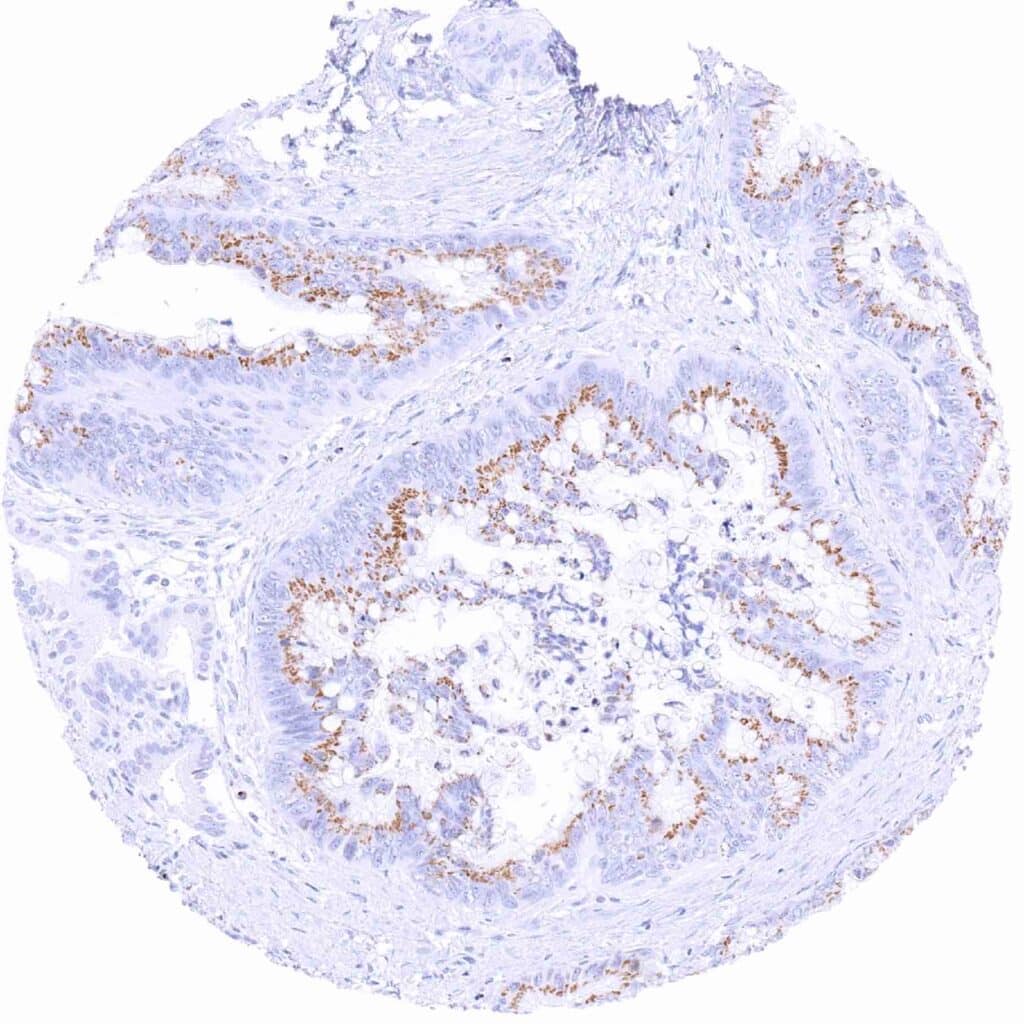

Pancreas – Ductal adenocarcinoma showing moderate granular perinuclear Prostein staining of neoplastic cells

Pancreas – Ductal adenocarcinoma with weak granular perinuclear Prostein staining of most tumor cells